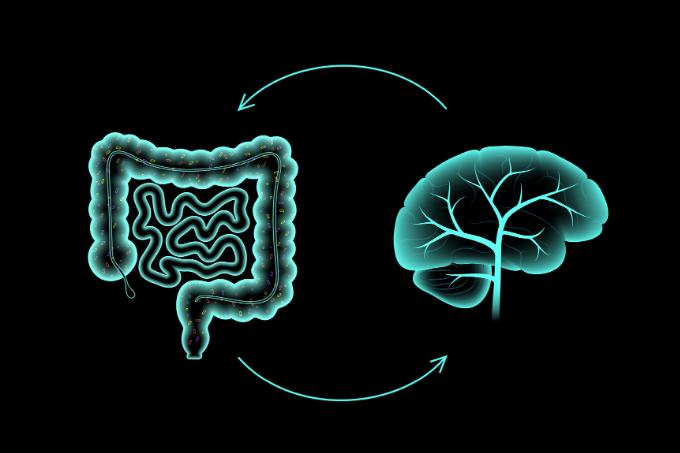

Anna Bach, encarregada de moderar l’esdeveniment, va destacar l’àmplia acceptació de la relació entre el sistema digestiu i el sistema nerviós i la necessitat que el col·lectiu farmacèutic estigui actualitzat per poder aconsellar a peu de taulell.

La Dra. Rosa Molina, va aprofundir durant la seva intervenció en la connexió intestí-cervell, explicant la relació entre el sistema nerviós, endocrí i immunitari i com la microbiota influeix en la funció cerebral. Entre els punts destacats va analitzar:

El webinar va concloure enfocant-se en la integració de coneixements sobre l’eix intestí-cervell per brindar una cura integral a la salut digestiva i emocional. Els ponents van ressaltar la importància de continuar investigant per avançar en la comprensió d’aquesta connexió fonamental entre el cos i la ment.